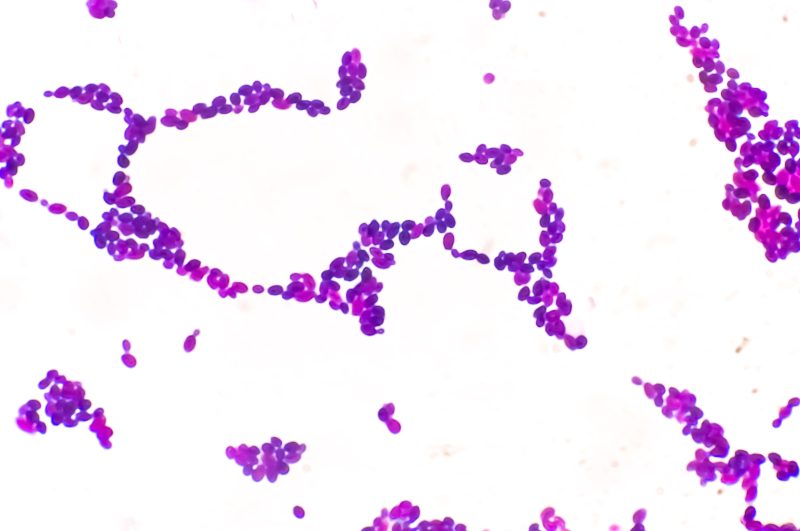

(NEXSTAR) – Health experts have been sounding the alarm for years on Candida auris, a drug-resistant fungus that’s hard to diagnose, hard to eliminate and hard to treat once it takes hold. The deadly fungus, also called C. auris, has nearly tripled this summer, and a new study published by Cambridge University Press shows who is getting hit hardest.

Candida auris is especially dangerous in health care settings, like hospitals and nursing facilities, where it can live on surfaces – like door knobs, counters and bed rails – for long periods of time. It’s resistant to antimicrobials, having developed a resistance to the drugs designed to kill it, making it hard to clean and eliminate.